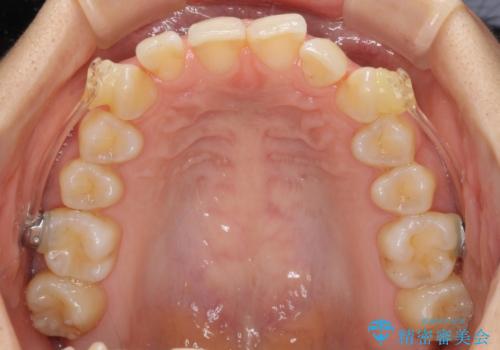

- 前歯の叢生と口元の閉じにくさを気にして来院された患者様です。

奥歯の咬み合わせを見ると、上顎が下顎に対して相対的に前方にありました。

口元の閉じにくさを改善するためには、上顎臼歯を後方に移動させた咬み合わせにする必要があります。

インビザライン単体で改善することも可能ですが、達成する可能性が高くないため、カリエールディスタライザーという補助装置を併用して、より確実性を上げることとしました。

奥歯の咬み合わせを改善しながら、並行してインビザラインで歯列を整えることとしました。

カリエールディスタライザーを併用したことで、確実かつ短期間で治療を終えることができました。